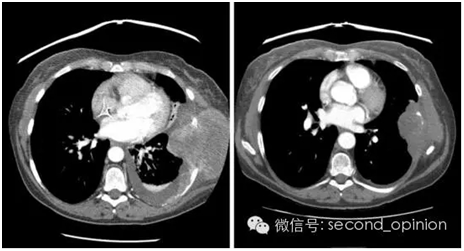

治疗两个周期后,患者肿瘤的最大线性测量值减少25%(图2,A和B),病情稳定且指标仅低于部分缓解的标准。继发性胸部疼痛减轻,呼吸困难有所缓解。治疗过程中,贝伐单抗引起的高血压(3级)需要进行对症治疗,患者因索拉非尼引起的2-3级手足综合征而将索拉非尼的剂量降低至每天200mg。除此之外,病人对治疗的耐受程度较好,治疗持续了7个月。

图2. 治疗前后影像学结果。A:治疗前胸部CT扫描:左侧胸壁肿瘤侵入肋骨,及左侧胸腔积液。B:治疗后胸部CT扫描:肿瘤体积和胸腔积液均降低。